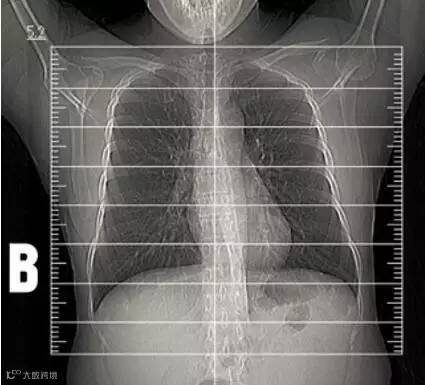

为了让医生更好的确定扫描范围,并使患者所受射线尽可能的少,定位像的准确性就必不可少了。为什么这么说呢?因为放射科医生是根据定位像来划定位线,确定扫描范围( 图B )的。所以第一次吸气尤为重要,倘若患者在第二次吸气比第一次吸气吸得多,肺的扩张程度不同,会导致原本的范围不够用,只能再加扫。简单地说,就像是吹气球,气吹的多气球大,气吹的少气球小。